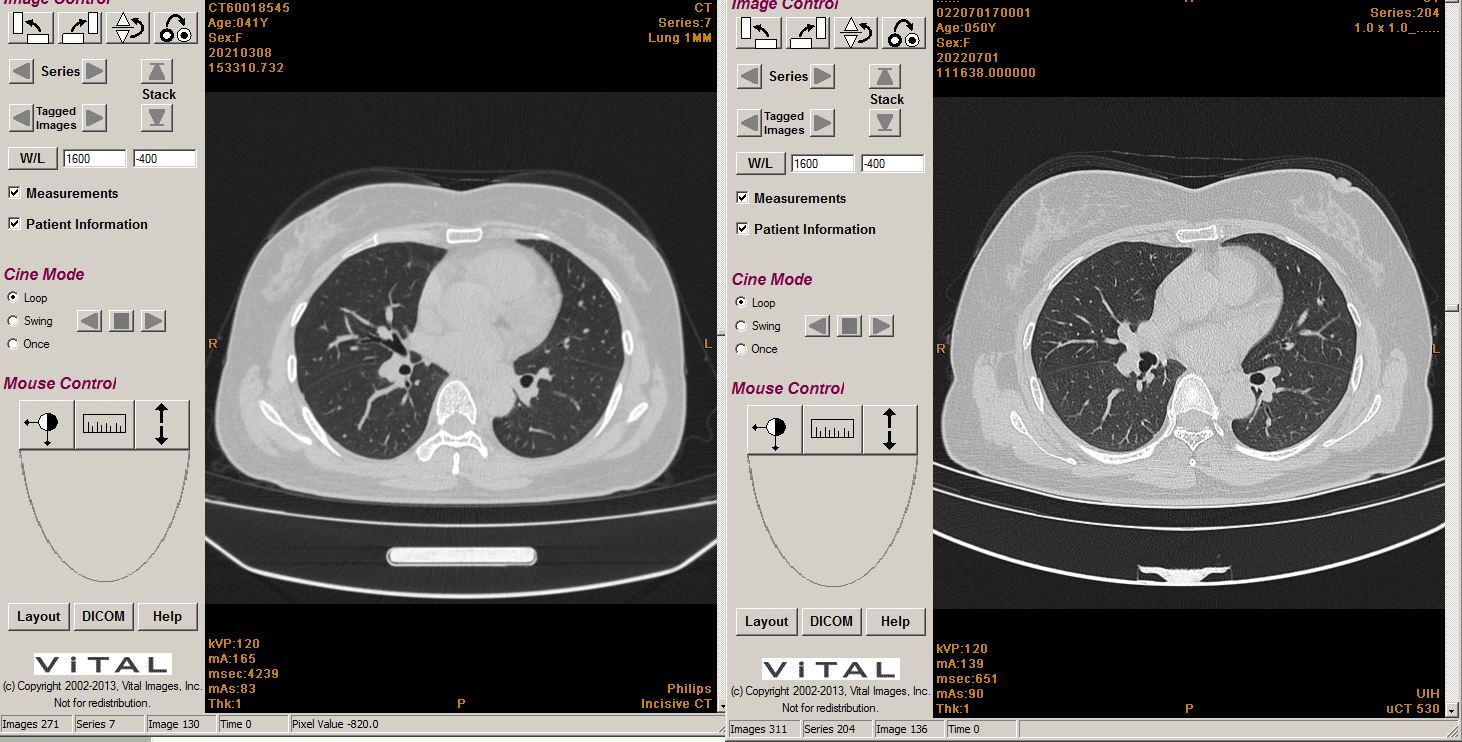

三甲

三甲

谭先华

副主任医师

武汉市第五医院

放射科

只言片语 之 (7)